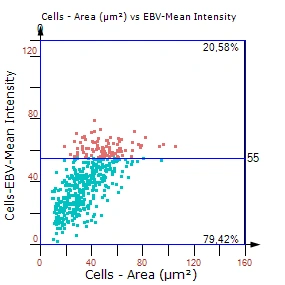

- Phenotype gating: Define cutoffs in area–intensity plots (Cellular Mask DAB mean intensity vs. area) to select positive immune cells.

- Immune phenotypes: Number and percentage of DAB-positive immune cells (e.g., CD45+, CD3+, CD20+) in whole tissue and within each morphological entity.

- Intensity metrics: Cellular mask area and mean intensity on the DAB channel.

Fig.1: Example plot